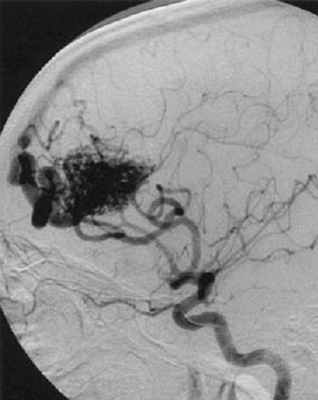

• Церебральная артериография. Этот тест считается самым лучшим способом диагностировать АВМ мозговых сосудов. Для теста в бедренную артерию вводят катетер, который достигает сосудов мозга, впрыскивают контрастное вещество, после чего делают серию рентгеновских снимков сосудов.

Артериовенозная мальформация (АВМ) — врожденная аномалия развития сосудистой системы головного мозга, которая представляет собой различной формы и величины клубки, образованные беспорядочным переплетением патологических сосудов. Функционально артериовенозная мальформация представляет собой прямое артерио-венозное шунтирование без промежуточных капилляров.

- Внутримозговые, субарахноидальные и внутрижелудочковые кровоизлияния. Это наиболее частое проявление, встречается в 50% - 70% случаев. Возрастной пик 20 - 40 лет. В среднем ежегодный риск кровоизлияния составляет около 3%. В течение первого года после первого эпизода, риск повторного кровоизлияния составляет 6%. Наличие небольшого узла, единственной дренажной вены, наличие аневризм на питающих сосудах, наличие варикозного расширения на дренажной вене или, наоборот, сужение её, глубокая локализация мальформации – увеличивают риск кровоизлияния.

Процедура проводится под общим наркозом. Производится прокол бедренной артерии, мягкий катетер вводится в сосуды, кровоснабжающие головной мозг. Микрокатетер проводится по питающему сосуду в сосуды узла АВМ. Под радиологическим контролем производится иньекция эмболизирующего материала. После заполнения узла АВМ, микрокатетер удаляется, и производится контрольная ангиография.